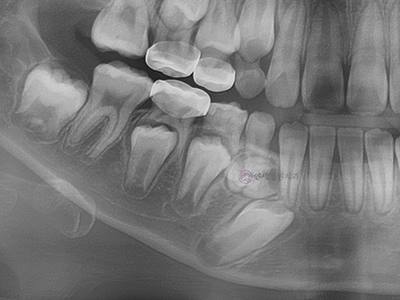

- 매복치 또는 과잉치

만 6~7세부터 유치가 빠지고 영구치가 나기 시작하는데요. 만약에 영구치가 올라오는 맹출 경로에 이상이 생긴다면, 치아가 올라오지 못하고 갇혀 매복치가 되거나, 정상 치아 개수보다 많은 과잉치로 인해 올라오지 못하거나, 교합에 문제가 발생할 수 있습니다. 자신도 모르는 사이 뼈 속에 묻혀있는 치아가 어긋날 수 있는 것입니다.

이런 경우에는 수술적 치료와 동반하여 과잉치를 제거하거나 매복된 치아를 교정적 힘을 이용해 제자리로 위치시키는 치료가 필요합니다.